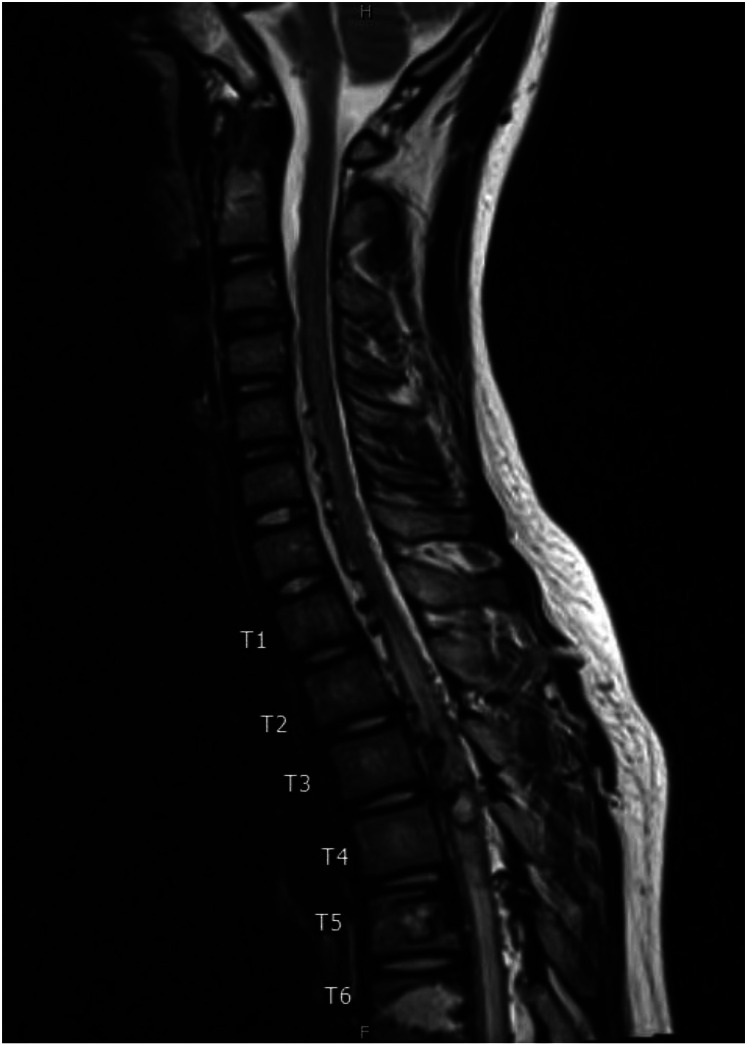

柯布综合征是一种罕见的神经皮肤病,其特征是多发性脊髓血管异常和影响相应皮节的血管性皮肤病变。我们报告了一例 12 岁男孩的病例,他的脊柱动静脉畸形(AVM)延伸至 T4-T5,3 年前部分栓塞后出现胸背部色素沉着斑,并伴有 2 天的背痛、下肢麻木和无力。他的脊柱和脊柱旁组织内有多个 III 型动静脉畸形,涉及 T4 至 T7 椎体,其中以 T4 和 T5 椎体最为广泛。位于主 AVM 瘤巢汇合处的最大动脉瘤是一个 4 毫米的脊髓前动脉瘤,在对主 AVM 瘤巢进行部分栓塞后,动脉瘤完全闭塞。本报告就柯布综合征的自然史、复发风险和治疗方案提供了宝贵的见解,有助于早期诊断和改善预后。

Cobb syndrome is a rare neurocutaneous disease characterized by multiple spinal vascular anomalies and vascular skin lesions affecting the corresponding dermatome. We present a case of a 12-year-old boy with history of spinal arteriovenous malformation (AVM) extending from T4-T5 status post partial embolization 3 years ago and hyperpigmented patch overlying his thoracic back region presenting with 2 days of back pain and lower extremity numbness and weakness. He had multiple Type III AVMs within the spinal and paraspinal tissues involving the T4-T7 vertebral elements, most extensively T4 and T5. The largest aneurysm located at the confluence of the main AVM nidus was a 4 mm anterior spinal artery aneurysm, which was embolized with partial embolization of the main AVM nidus, resulting in complete aneurysm occlusion. This report provides valuable insight on the natural history, recurrence risk, and treatment options of Cobb syndrome to aid in early diagnosis and improve outcomes.